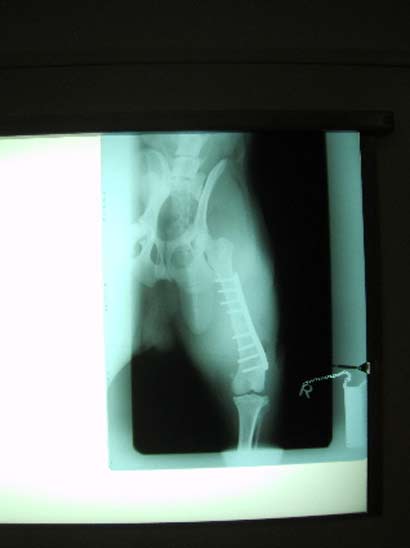

Da Asco sich immer mehr daran gewöhnte auf 3 Beinen zu laufen, hatten wir schon das Schlimmste erwartet und wurden durch ein Röntgenbild leider bestättigt.

Der gebrochene Knochen wuchs einfach nicht zusammen. Es war zu keiner Heilung im Frakturbereich gekommen. Die Frakturenden hatten sich abgedeckelt und waren vollständig instabil. Es war klar, dass Jack mit diesem Bein nie würde laufen können!

Die bittere Diagnose war also eine neuerliche OP, die über eine stärkere Platte, einen stützenden Nagel und zusätzliches, knochenbildendes Gewebe die ersehnte Heilung bringen sollte! Es tut uns in der Seele weh, diesem hochintelligenten und lebensfrohen Hund dies ein weiteres Mal antun zu müssen, aber es half nichts.